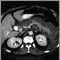

Pancreatitis, acute - CT scan